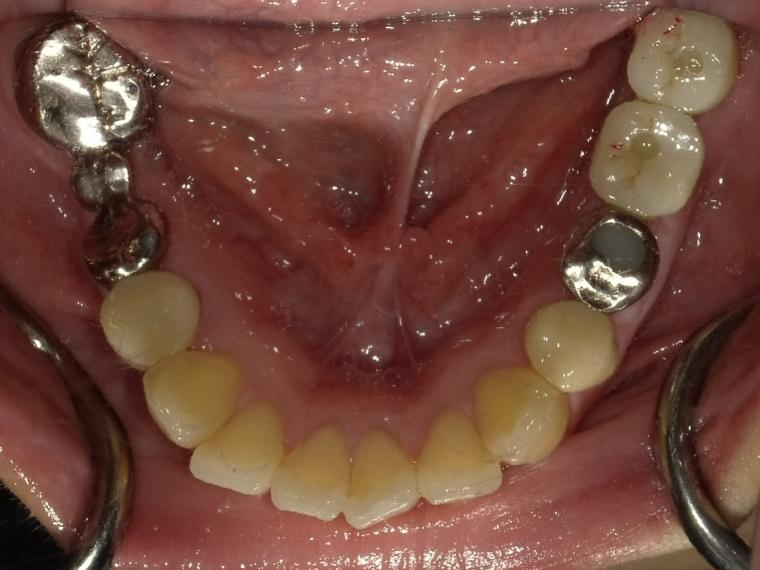

BEFORE

36歳女性/下2本欠損/インプラント埋込手術

左下のブリッジが割れそうでご来院の患者さんです。

保存状態が厳しかった為、第一大臼歯と第二大臼歯が抜歯となりました。

第一大臼歯と第二大臼歯をインプラント、第二小臼歯をクラウンでの治療を希望されました。